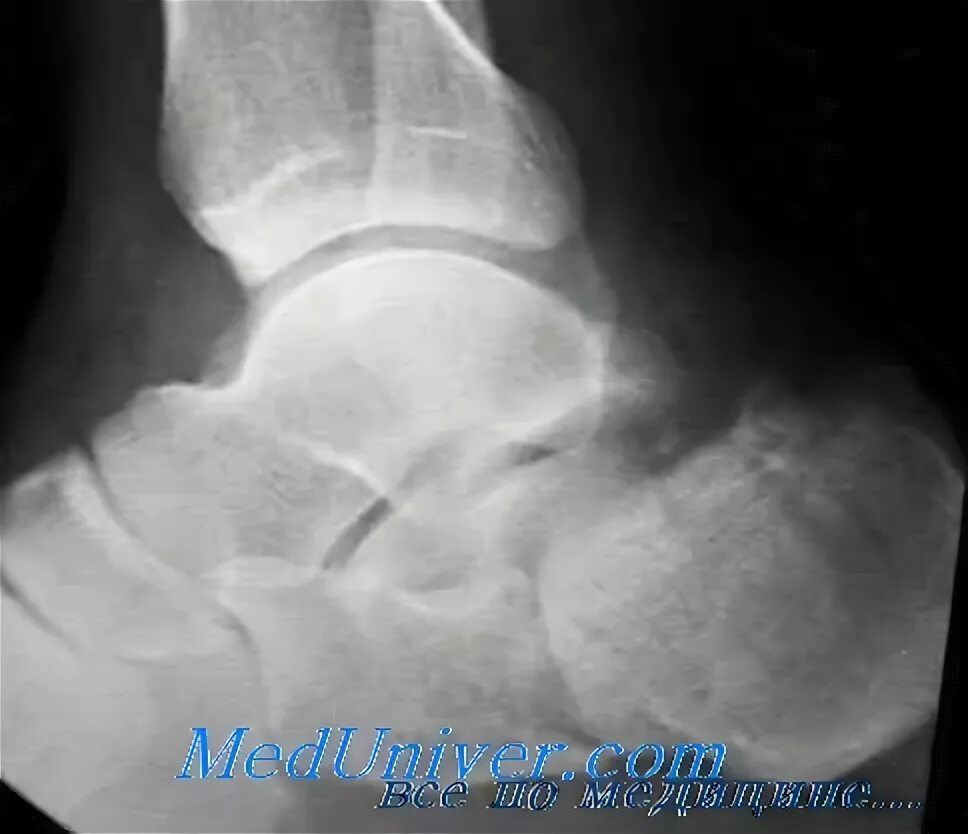

Пяточный перелом без смещения